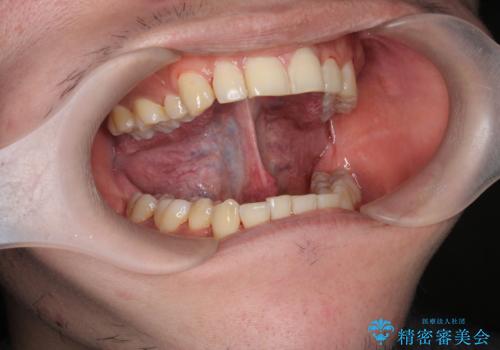

[ 滑舌の改善 ] 即日可能な舌小帯形成

担当医 大元洋佑

![[ 滑舌の改善 ] 即日可能な舌小帯形成の症例 治療前](https://seimitsushinbi.jp/wp/wp-content/uploads/2021/10/e94e53e814f8e1b96166b92cd579ec1d-500x350.jpg?v=1633515968)

![[ 滑舌の改善 ] 即日可能な舌小帯形成の症例 治療後](https://seimitsushinbi.jp/wp/wp-content/uploads/2021/10/152d311fe2f312a807ed1178fbc60d44-500x350.jpg?v=1633515980)